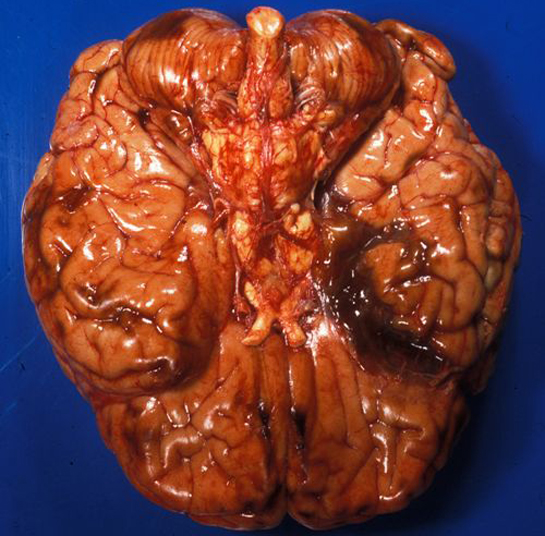

Beyin iltihabı, merkezi sinir sisteminin iltihaplanmasıdır ve çeşitli enfeksiyonlar, otoimmün hastalıklar ve travmalar gibi etkenlerden kaynaklanabilir. Belirtileri arasında ateş, baş ağrısı ve zihinsel değişiklikler bulunur. Doğru tanı ve tedavi, komplikasyonları önlemek için kritik öneme sahiptir.

Beyin iltihabı, beynin veya merkezi sinir sisteminin iltihaplanması durumunu ifade eder. Bu durum, çeşitli enfeksiyonlar, otoimmün hastalıklar ve diğer etkenler sonucu ortaya çıkabilir. Beyin iltihabı, bazen ciddi sağlık sorunlarına yol açabileceğinden, belirtilerinin doğru bir şekilde tanınması ve tedavi edilmesi oldukça önemlidir. 1. Beyin İltihabının Nedenleri Beyin iltihabının oluşumunda birçok faktör etkili olabilir. Bu faktörler arasında: